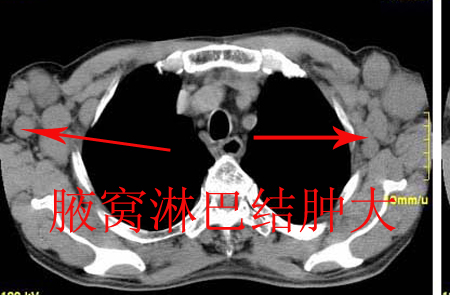

隆突下淋巴结,双侧腋下淋巴结肿大,右侧胸腔少量积液,支持非何杰金氏淋巴瘤。

以下是引用jiangjing在2007-5-13 22:04:00的发言:[br]隆突下淋巴结、后下纵隔食管旁(心后)淋巴结肿大,并见相互融合,双侧腋下淋巴结肿大,右侧胸腔少量积液,支持非何杰金氏淋巴瘤。

以下是引用jiangjing在2007-5-13 22:04:00的发言:[br]隆突下淋巴结、后下纵隔食管旁(心后)淋巴结肿大,并见相互融合,双侧腋下淋巴结肿大,右侧胸腔少量积液,支持非何杰金氏淋巴瘤。

以下是引用jiangjing在2007-5-13 22:04:00的发言:[br]隆突下淋巴结、后下纵隔食管旁(心后)淋巴结肿大,并见相互融合,双侧腋下淋巴结肿大,右侧胸腔少量积液,支持非何杰金氏淋巴瘤。

以下是引用shenhs在2007-5-13 22:23:00的发言:[br][quote]以下是引用jiangjing在2007-5-13 22:04:00的发言:[br]隆突下淋巴结、后下纵隔食管旁(心后)淋巴结肿大,并见相互融合,双侧腋下淋巴结肿大,右侧胸腔少量积液,支持非何杰金氏淋巴瘤。

以下是引用jiangjing在2007-5-13 22:04:00的发言:[br]隆突下淋巴结、后下纵隔食管旁(心后)淋巴结肿大,并见相互融合,双侧腋下淋巴结肿大,右侧胸腔少量积液,支持非何杰金氏淋巴瘤。

以下是引用jiangjing在2007-5-13 22:04:00的发言:[br]隆突下淋巴结、后下纵隔食管旁(心后)淋巴结肿大,并见相互融合,双侧腋下淋巴结肿大,右侧胸腔少量积液,支持非何杰金氏淋巴瘤。

以下是引用jiangjing在2007-5-13 22:04:00的发言:[br]隆突下淋巴结、后下纵隔食管旁(心后)淋巴结肿大,并见相互融合,双侧腋下淋巴结肿大,右侧胸腔少量积液,支持非何杰金氏淋巴瘤。

以下是引用jiangjing在2007-5-13 22:04:00的发言:[br]隆突下淋巴结、后下纵隔食管旁(心后)淋巴结肿大,并见相互融合,双侧腋下淋巴结肿大,右侧胸腔少量积液,支持非何杰金氏淋巴瘤。